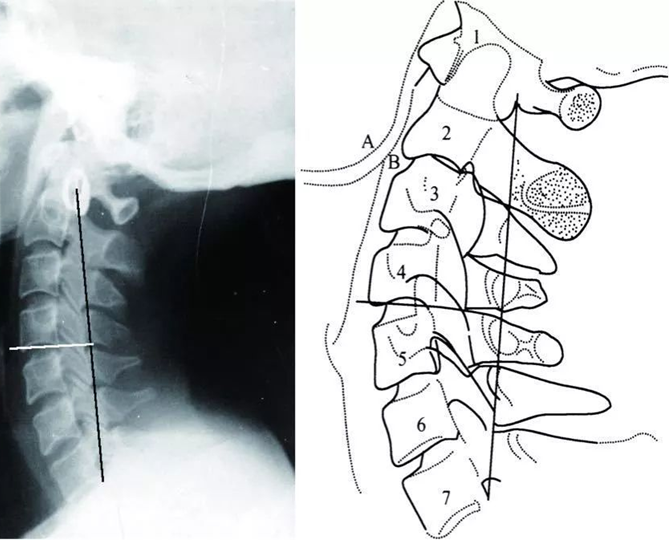

牵引角度包括前屈位、中立位和后伸位,即牵引绳分别位于头部的斜前方、正上方和后上方,其中,前屈位牵引最为常见。在治疗中,一般先根据影像资料找到发生病变的颈椎节段,再确定牵引的位置与角度。

颈椎共有7节

牵引时要将下巴和后脑勺包住,图为前屈位牵引中不同的牵引角度